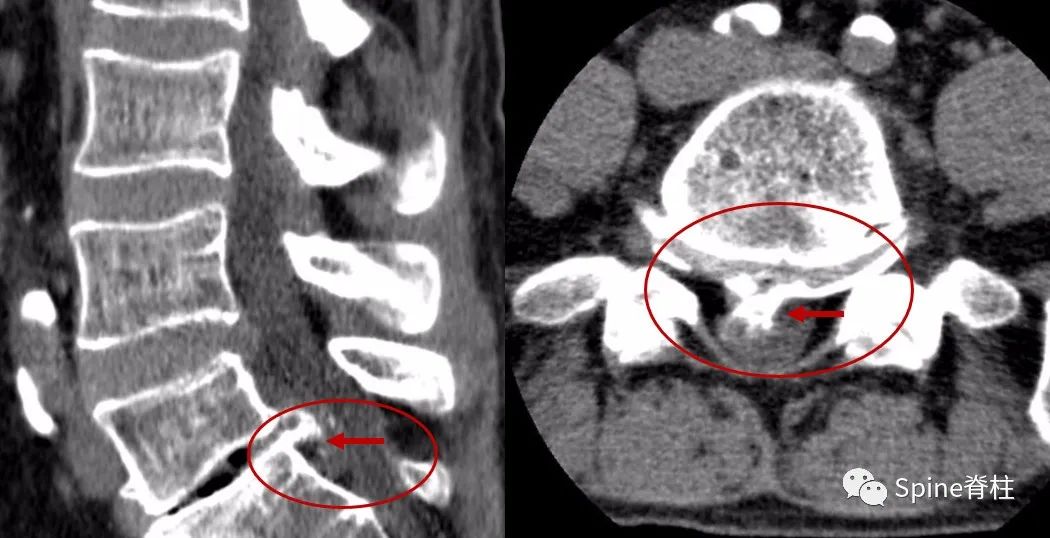

另外,需要明确的是,CT和MRI都是躺着拍的,而X线是站者拍的。对于需手术的腰突症患者,拍X线片可从整体评估腰椎结构、序列,尤其对腰椎滑脱的诊断意义更大,因为平躺后滑脱可能会自行复位,此时拍CT和MRI会导致漏诊。另外,MRI对骨质的分辨要差于CT,对于伴有骨化的椎间盘突出,手术难度要明显大于单纯的软性髓核突出。术前CT可甄别骨化的椎间盘,有助于评估手术难度(图10)。

腰椎间盘突出症状表现,腰椎间盘突出症疼痛最佳止痛方法

图10:腰椎CT示L5-S1椎间盘突出伴骨化

因此,建议需手术治疗的腰椎间盘突出症患者,完善腰椎X线、CT和MRI平扫,可全面评估腰突情况,为顺利手术保驾护航。